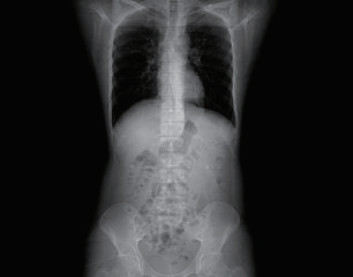

1 一般资料患者,男性,32岁,职员,因“误吞金属钉状物7 d”就诊。患者7 d前误吞入金属钉状物一根(大小约3 cm),患者无明显不适症状,未诊治。4 d前出现下腹隐痛,行急诊全腹CT检查,见图 1,行急诊胃镜检查未见明显异物。后复查腹部CT示异物进入小肠内(图 2),普外科会诊建议随访。2 d前复查腹部CT(图 3),继续保守治疗。1 d前患者为行异物取出入院,复查腹部CT可见异物至结肠内(图 4)。急诊予以聚乙二醇电解质散导泻清肠,行无痛肠镜下异物取出术。本文已通过本院伦理委员会审批,伦理审批号为:(2021)伦审研第(0252)号,并通过免除知情同意申请。完善术前检查,进行药物导泻清肠时,关注患者有无腹痛等现象,以免因服用药物清肠,肠蠕动加快,尖锐异物在消化道内随蠕动前行,尖端嵌插在肠壁中而停滞不前,并随着后方内容物的推进,加深尖锐异物刺入肠壁,最终导致穿孔及出血的发生。本例患者安置在独立单人间进行肠道准备,不定时进行腹部查体及观察排泄物的性状,早期发现穿孔、出血指征,以便尽早进行外科手术干预。与此同时,内镜中心医护人员联合外科、放射科、麻醉科医生制定诊疗方案,若发生此类情况,立即予急诊行腹部X线或CT检查,一旦确定出现穿孔或出血等情况,即刻行急诊手术治疗。

| 图 2 腹部CT示小肠内条索状致密影,周边放射状明显,邻近肠系膜未见渗出和积气 |

| 图 3 腹部CT示升结肠起始部管腔内致密影,约3.2 cm, 周边放射状明显,邻近肠系膜未见渗出和积气 |

| 图 4 腹部CT示回盲部致密影,提示异物 |